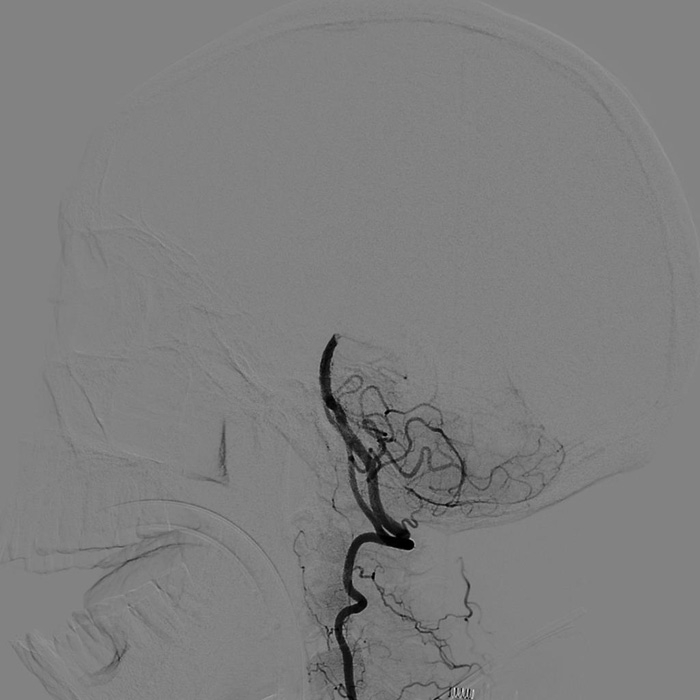

??? 22:10? 王大伯病情進一步加重,神經(jīng)外科戴偉民主任醫(yī)師團隊、麻醉師和介入室的醫(yī)護人員全部已經(jīng)到位。全腦血管造影顯示栓塞部位在基底動脈末端,雙側(cè)小腦上動脈及雙側(cè)大腦后動脈開口處完全閉塞。

手術(shù)前血管造影提示雙側(cè)小腦上動脈及雙側(cè)大腦后動脈開口處完全閉塞

取栓后造影顯示雙側(cè)小腦上動脈及雙側(cè)大腦后動脈充盈良好